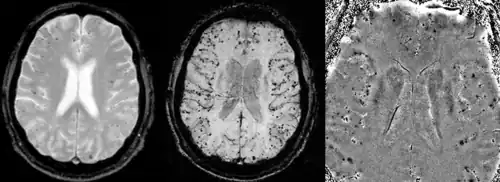

Vascular dementia and cerebral amyloid angiopathy (CAA)

Gradient recalled echo (GRE) imaging is the conventional way to detect hemorrhage in CAA, however SWI is a much more sensitive technique that can reveal many micro-hemorrhages that are missed on GRE images.[7] A conventional gradient echo T2*-weighted image (left, TE=20 ms) shows some low-signal foci associated with CAA. On the other hand, an SWI image (center, with a resolution of 0.5 mm x 0.5 mm x 2.0 mm, projected over 8mm) shows many more associated low-signal foci. Phase images were used to enhance the effect of the local hemosiderin build-up. An example phase image (right) with yet higher resolution of 0.25 mm x 0.25 mm x 2.0 mm shows a clear ability to localize multiple CAA-associated foci.